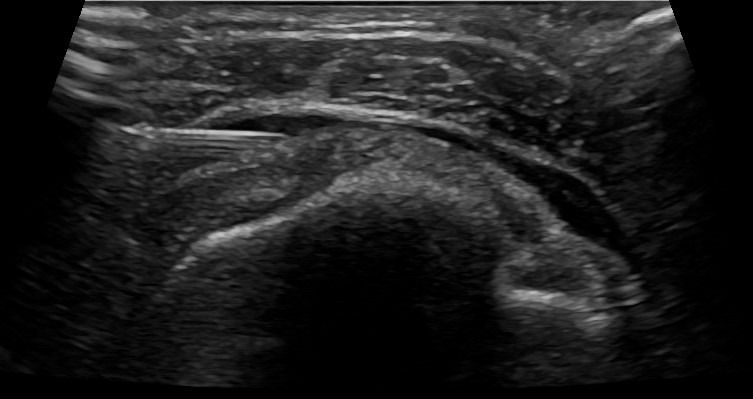

Η καθοδήγηση του υπερήχου εγγυάται τη σωστή και ασφαλή τοποθέτηση του κορτικοστεροειδούς εντός του θυλάκου, αποφεύγοντας την πιθανή έγχυση στον τένοντα, η οποία μπορεί να προκαλέσει φθορά του.

Σε συνδυασμό με την αντιφλεγμονώδη δράση του κορτικοστεροειδούς, η υπερηχογραφική καθοδήγηση παρέχει τη δυνατότητα υδροδιάτασης του θυλάκου πριν την έγχυση του κορτικοστεροειδούς. Η υδροδιάταση περιλαμβάνει έγχυση φυσιολογικού ορού και τοπικού αναισθητικού προκειμένου να εξουδετερωθούν οι συμφύσεις εντός του θυλάκου.